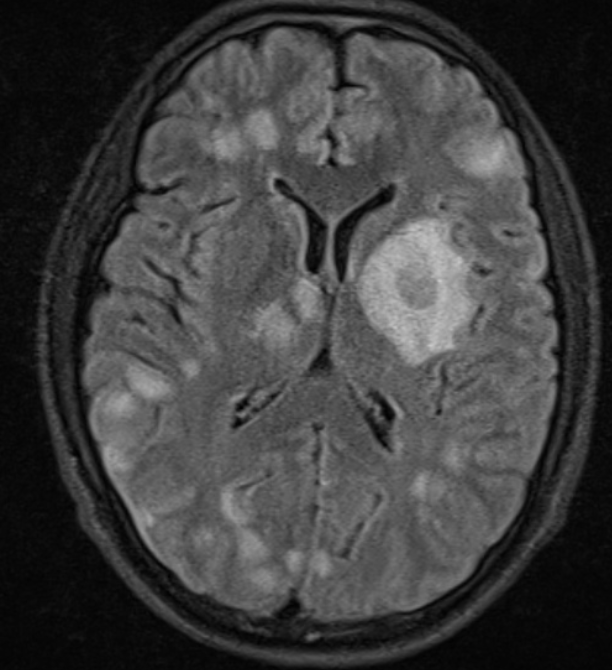

Note the multiple sites of oedema and haemorrhage, involving the brain stem and corpus callosum as well as subcortical white matter and left cerebral peduncle. High FLAIR signal is also seen in the dorsal midbrain. EVD insitu.

Case Discussion

Diffuse axonal injury can be subtle on CT but have devastating consequences for the patient. This is a case of grade III injury (involvement of brainstem) and carries a poor prognosis.

Diffuse axonal injury (DAI), also known as traumatic axonal injury (TAI), is a severe form of traumatic brain injury due to shearing forces. It is a potentially difficult diagnosis to make on imaging alone, especially on CT as the finding can be subtle, however, it has the potential to result in severe neurological impairment.

The diagnosis is best made on MRI where it is characterised by several small regions of susceptibility artifact at the grey-white matter junction, in the corpus callosum, and in more severe cases in the brainstem, surrounded by FLAIR hyperintensity.

Diffuse axonal injury is characterised by multiple focal lesions with a characteristic distribution: typically located at the grey-white matter junction, in the corpus callosum and in more severe cases in the brainstem (see: grading of diffuse axonal injury).

The appearance depends on whether or not the lesions are overtly haemorrhagic. Haemorrhagic lesions will be hyperdense and range in size from a few millimetres to a few centimetres in diameter. Non-haemorrhagic lesions are hypodense. They typically become more evident over the first few days as oedema develops around them. They may be associated with significant and disproportionate cerebral swelling.

CT is particularly insensitive to non-haemorrhagic lesions (as defined by CT) only able to detect 19% of such lesions, compared to 92% using T2 weighted imaging 4. When lesions are haemorrhagic, and especially when they are large, then CT is quite sensitive. As such, it is usually a safe assumption that if a couple of small haemorrhagic lesions are visible on CT, the degree of damage is much greater.

MRI is the modality of choice for assessing suspected diffuse axonal injury even in patients with entirely normal CT of the brain 5,6. MRI, especially SWI or GRE sequences, exquisitely sensitive to paramagnetic blood products may demonstrate small regions of susceptibility artefact at the grey-white matter junction, in the corpus callosum or the brain stem. Some lesions may be entirely non-haemorrhagic (even using high field strength SWI sequences). These will, however, be visible as regions of high FLAIR signal.